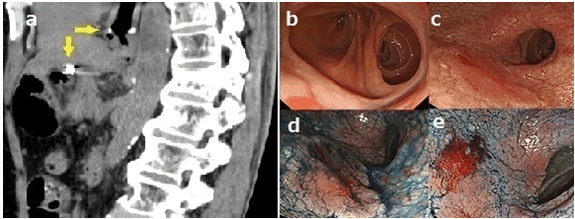

An 83-year-old male had undergone PG with jejunal interposition for mucosal gastric cancer at another hospital (Figure 1a-b). Approximately two years later, he requested to undergo his first follow-up upper gastrointestinal endoscopy. Physical examination and routine laboratory examinations revealed no abnormalities. Conventional endoscopy and chromoendoscopy with indigo carmine dye showed a large, flat, elevated, soft lesion, approximately 40 mm in diameter, on the distal gastric remnant (Figure 1c-e). This lesion was biopsied, revealing a well-differentiated adenocarcinoma. Endoscopic ultrasonography was performed to evaluate the invasion depth, and the cancer was classified to be an intramucosal carcinoma with negligible risk of lymph node metastasis. We explained to the patient that ESD is an investigational treatment for this lesion according to the expanded indication mentioned in the Japanese gastric cancer treatment guidelines [4], and he chose to undergo ESD instead of surgery. Curative en bloc resection of the lesion was successfully achieved by ESD using the IT knife-2 (KD-611 L; Olympus Medical Systems, Tokyo, Japan) and the transparent hood (F-030; TOP Co., Ltd., Tokyo, Japan) (Figure 2a-e). The procedure time was 50 min. The resected specimen revealed well-differentiated adenocarcinoma confined to the mucosa without vessel infiltrations (Figure 2f). The resection margins were negative. Neither recurrence nor metastasis of GRC has been detected at present, i.e., two years later.

Figure 1: (a) Abdominal computed tomography scan showed anastomosed parts post-proximal gastrectomy with jejunal interposition (yellow arrows), (b) Conventional view of the anastomosed part post-proximal gastrectomy with jejunal interposition, (c) Conventional view of early gastric cancers (approximately 40 mm in diameter), (d) Chromoendoscopic view of the distal side of early gastric cancer stained with indigo carmine, and (e) Chromoendoscopic view of the proximal side of early gastric cancer stained with indigo carmine.